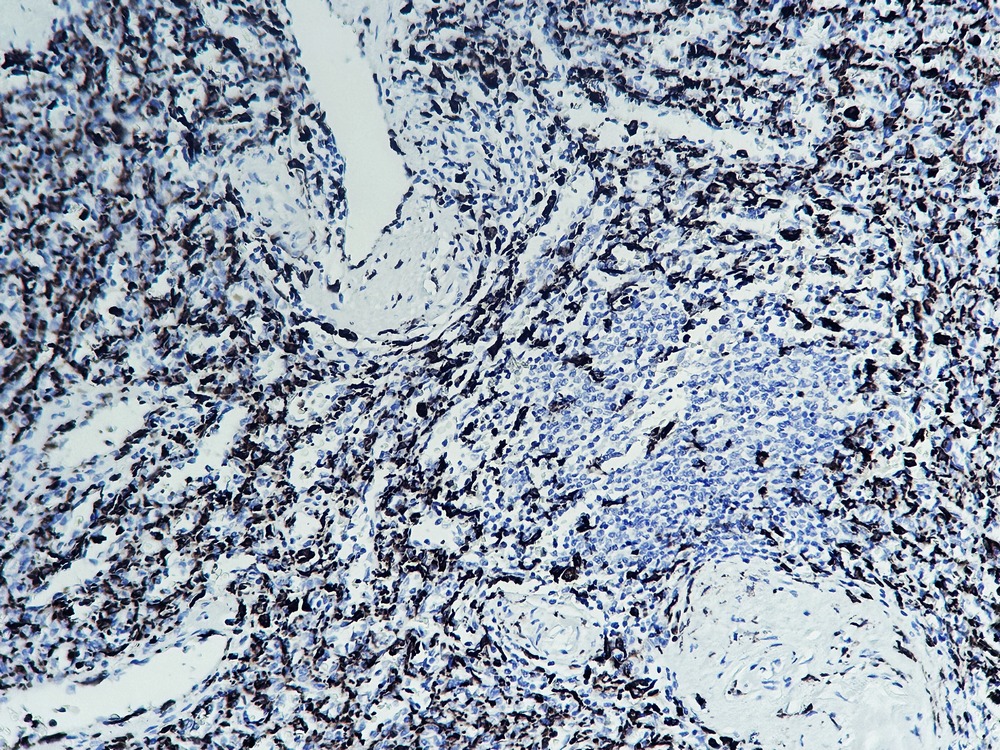

2. Human stomach tissue was stained with Anti-Iba 1 Antibody.

3. Human spleen tissue was stained with Anti-Iba 1 Antibody.